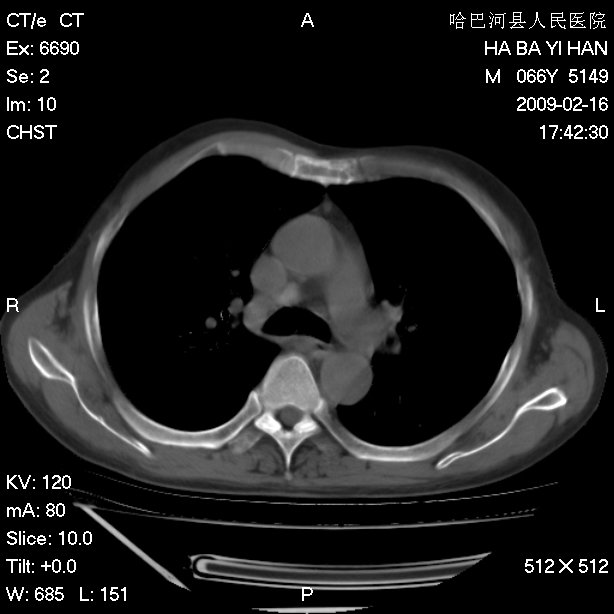

以下是引用huangxun4321在2009-2-16 20:18:00的发言:[br]部分病灶可见硬化边,部分可见骨质破坏消失,部分病灶内可见骨脊,说明病灶内既有良性病变,又有恶性病变,考虑骨巨细胞瘤恶变,未除骨纤恶变,畸形性骨炎少见,亦要考虑.

以下是引用731208在2009-2-16 20:31:00的发言:[br]考虑恶性胸膜间皮瘤并肋骨,脊柱转移。

以下是引用yijiansheng在2009-2-16 20:16:00的发言:[br]考虑恶性胸膜间皮瘤并肋骨,脊柱转移。

以下是引用形影不离在2009-2-16 19:55:00的发言:[br]考虑多发性转移瘤。